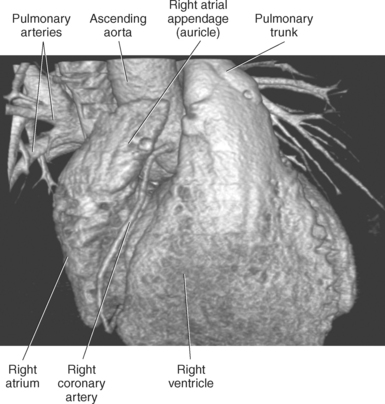

The right atrium forms the right border of the heart and receives deoxygenated blood from the body via the superior and inferior venae cavae and from the coronary sinus and cardiac veins that drain the myocardium. A small muscular embryonic appendage, the right auricle, projects upward and toward the left from the right atrium, covering the root of the aorta (Figure 6.40). The right ventricle lies on the diaphragm and comprises the largest portion of the anterior surface of the heart. It receives deoxygenated blood from the right atrium and forces it into the pulmonary trunk for conveyance to the lungs. Projecting off the inferior surface of the ventricular walls are conical-shaped projections of cardiac muscle called papillary muscles that anchor the cusps of the tricuspid valve to the right ventricle (Figure 6.39). The left atrium lies posterior to the right atrium and is the most posterior surface of the heart. It also has an embryonic appendage, the left auricle, that projects to the left of the pulmonary trunk over the superior surface of the heart. The left atrium receives oxygenated blood directly from the lungs via the four pulmonary veins (two on each side). The left ventricle forms the apex, left border, and most of the inferior surface of the heart. It receives oxygenated blood from the left atrium and pumps it into the aorta for distribution throughout the systemic circuit. The myocardium of the left ventricle is normally three times thicker than that of the right ventricle, reflecting the force necessary to pump blood to the distant sites of the systemic circulation (Figures 6.41 through 6.52). Two papillary muscles project from the ventricular walls to anchor the bicuspid valve to the ventricle (Figures 6.39 and 6.47).

The two main coronary arteries are the first vessels to branch off the ascending aorta (Figures 6.91 and 6.92). The right coronary artery arises from the base or root of the aorta (right aortic sinus) and passes anteriorly between the pulmonary trunk and right atrium to descend in the coronary (atrioventricular) groove. As it reaches the diaphragmatic surface, it gives off a right marginal branch that runs toward the apex of the heart. The right coronary artery then turns to the left and enters the posterior interventricular groove, where it gives off the posterior interventricular branch (posterior descending artery). The posterior interventricular branch continues to descend along the interventricular groove toward the apex, where it anastomoses with the left anterior descending artery of the left coronary artery. The right coronary artery and its branches supply the right atrium, right ventricle, interventricular septum, and the sinoatrial (SA) and atrioventricular (AV) nodes. It also supplies a portion of the left atrium and ventricle (Figures 6.92 through 6.96). The left coronary artery arises from the left aortic sinus and passes to the left between the pulmonary trunk and left atrium to reach the coronary groove (Figures 6.91 and 6.92). Soon after reaching the coronary groove, the left coronary artery divides into the circumflex and left anterior descending (interventricular) arteries. The circumflex artery winds around the left border of the heart to the posterior surface, where it gives off the left marginal artery. The left anterior descending artery (LAD) descends in the anterior interventricular groove toward the apex of the heart, where it reaches the diaphragmatic surface to anastomose with the posterior descending artery. The left coronary artery and its branches supply the interventricular septum, including the AV bundles, and most of the left ventricle and atrium (Figures 6.97 through 6.99).